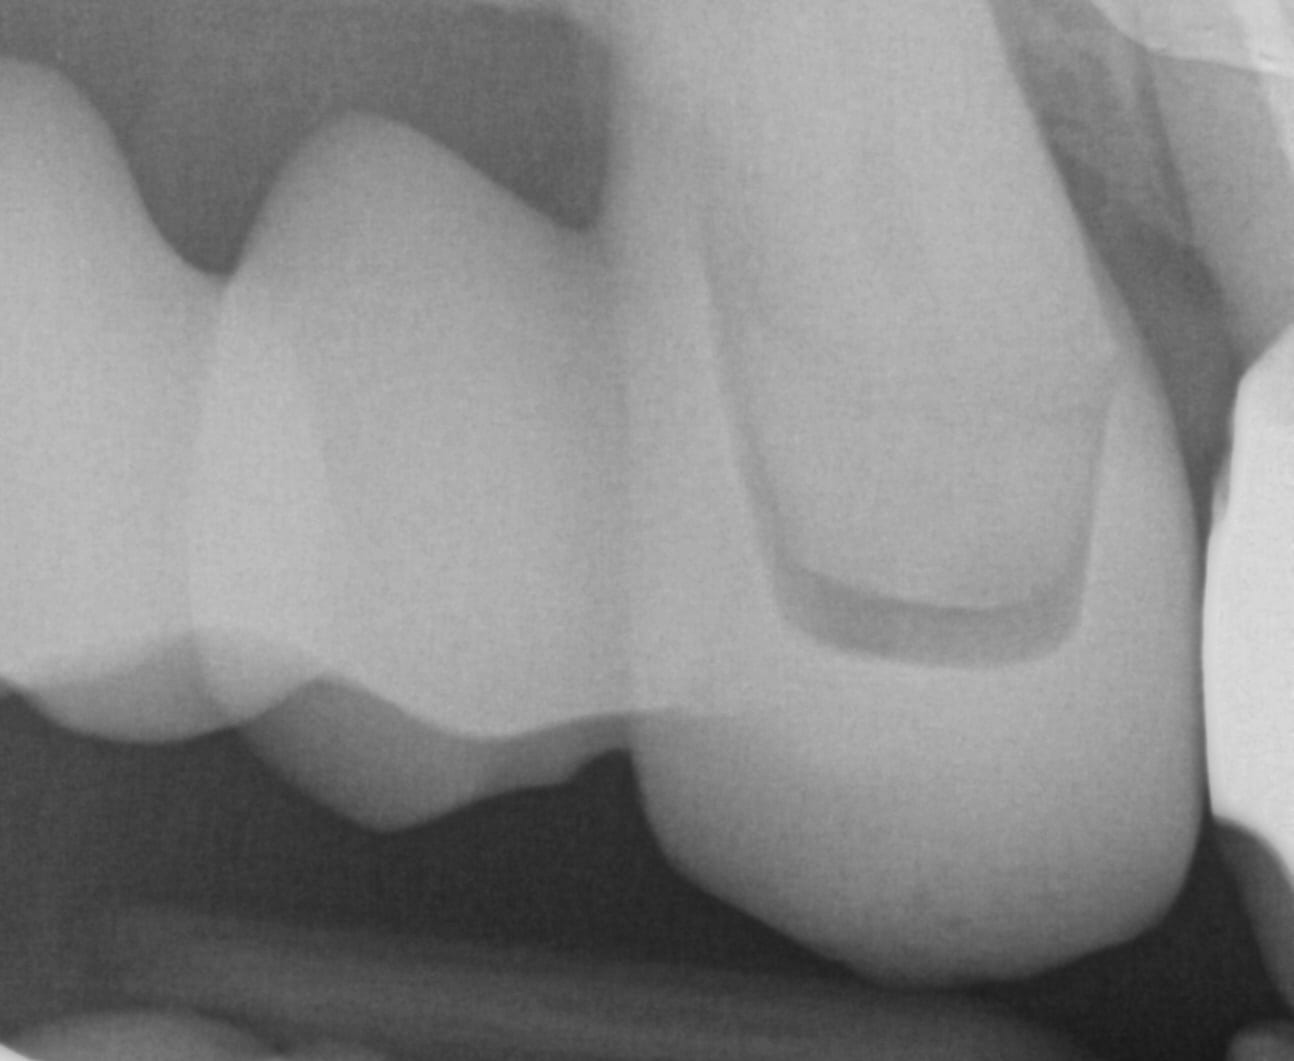

You can then take the prosthesis out of the mouth and continue imaging it and roll over to the intaglio and capture that information.

You can even reline the prosthesis to get the best adaptation possible, scan that, clone the case, and then use the edit tool to crop out everything but the intaglio. What remains is the edentulous ridge that is properly mounted to the opposing arch where you can start designing the desired final restoration.